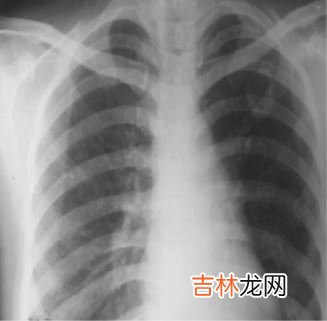

【系统性红斑狼疮合并肺结核七例】 7例患者疾病经过相似,除1例外初期均按普通细菌感染治疗效果不佳,入院后综合临床及化验资料分析,考虑发热均非sle本身所致,鉴于抗生素无效,痰真菌检查多次为阴性,遂考虑结核感染 。有2例入院时行x线胸片检查即确诊为浸润型肺结核,其中1例尚合并肺真菌感染 。另2例患者前2次x线胸片检查除报告肺纹理稍增多外,无特殊发现,第3次复查x线胸片时(2周后)方出现典型的分布均匀、密度一致的粟粒状结节影而得以确诊 。另3例患者前2次胸片分别报告“右肺外段感染”,“双肺感染,右侧胸腔积液”及“肺纹理增多” 。请呼吸科专家会诊,重阅胸片后,均被发现有结核的征象 。第3次复查时,1例胸片出现了典型的粟粒型肺结核改变,1例出现了浸润型肺结核改变,另1例胸片仍不典型,但经抗痨治疗证实 。7例经足量四联抗痨,其中1例抗痨45d体温才开始明显下降,另1例15d体温不降,转院后继续抗痨,但仍死于粟粒型肺结核 。其余体温分别于7~26d明显下降 。抗痨总疗程均达1年至1年半 。有1例于抗痨后20d面部蝶形红斑加重,另1例于4个月后再发蝶形红斑,且皮疹逐渐增多泛发,复查igg由13.4g/l升至26.1g/l;ana由1∶20上升至1∶160 。2例激素用量均不变,停异烟肼后皮疹逐渐消退 。7例患者经抗痨治疗证实合并有肺结核,对此我们的经验是:1当发热及咳嗽、咯痰不能用sle本身解释,而痰真菌检查阴性且强有力抗感染治疗无明显效果时,要考虑到可能合并结核 。2x线胸片在诊断上有重要价值,本组病例均为从发热→抗菌治疗→真菌培养→痰培养→摄片,若一开始即摄片并请专家会诊,一般不会误诊 。此外初期胸片无特殊发现时,应定期复查,本文有5例均是第3次复查胸片时才出现典型的结核征象 。37例sle治疗过程中出现的肺结核均为急性粟粒型或浸润型肺结核 。4对于sle患者抗痨治疗显效较慢,抗痨应足量足疗程,如1例经抗痨后45d体温才开始明显下降 。5警惕异烟肼诱发狼疮的问题,本组有2例可能有此现象 。